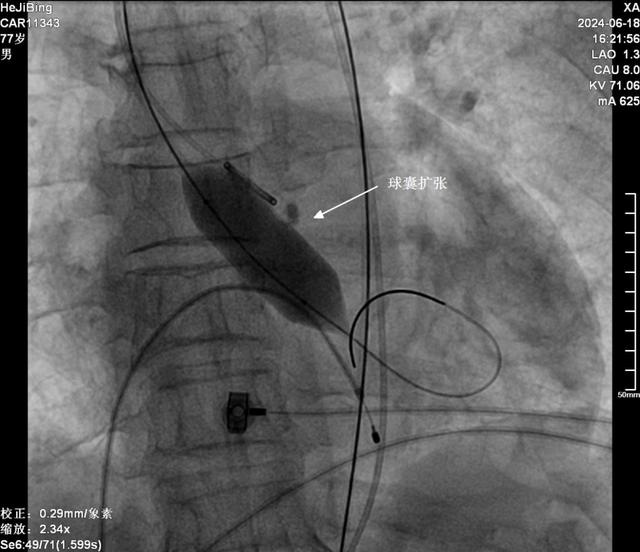

该手术经股动脉穿刺,球囊扩张狭窄的主动脉瓣后,经导管植入主动脉瓣膜支架,相比外科开胸手术,创伤小,感染风险小,恢复快,特别适合高龄、有基础疾病患者,且疗效确切。

这是一种微创介入导管技术。手术医生将带有人工瓣膜的导管通过血管(通常是腹股沟处的股动脉),推进到主动脉瓣的区域,在处于适当位置时导管缓慢释放,此时人工瓣膜被打开并开始起作用。